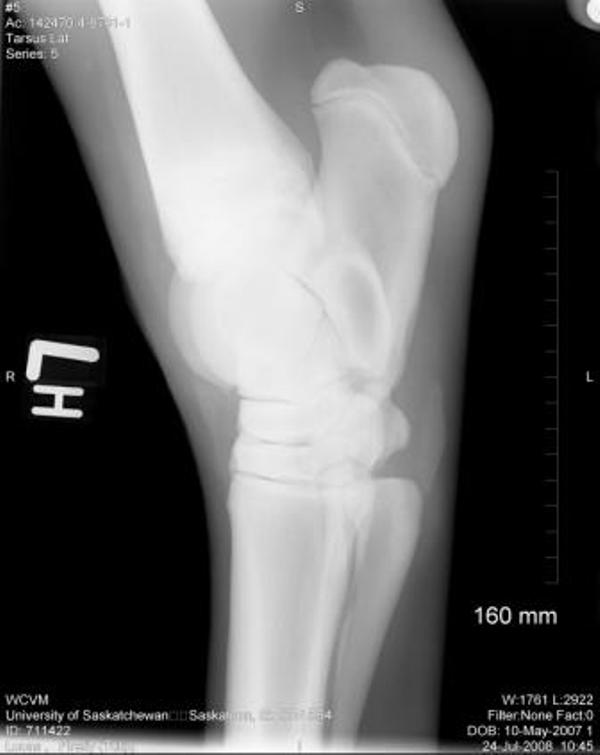

Thank you so much for your assistance, it is really appreciated!! I finally have the cd of the x-rays and will be posting them here. Again, thank you!! The first 2 are stifle pictures, the rest are of the hock.

Right stifle

Thanks Dr. O!! I really appreciate your taking a look at this. I do have Dr. Rantanen's report which is as follows:

Interpretation:

The most proximal portion of the right medial tibial spine was separated by an irregular fracture line. The fragment was still close to its anatomic position.

There was no soft tissue swelling or secondary joint disease present at this time.

Comment:

With the absence of clinical signs of lameness, normal flexion and no soft tissue swelling at this time, this fracture most likely occurred at a young age. It may be an incidental finding in this horse. Success in training would confirm that this fracture most likely occurred at a young age and may be tolerated without surgical intervention.